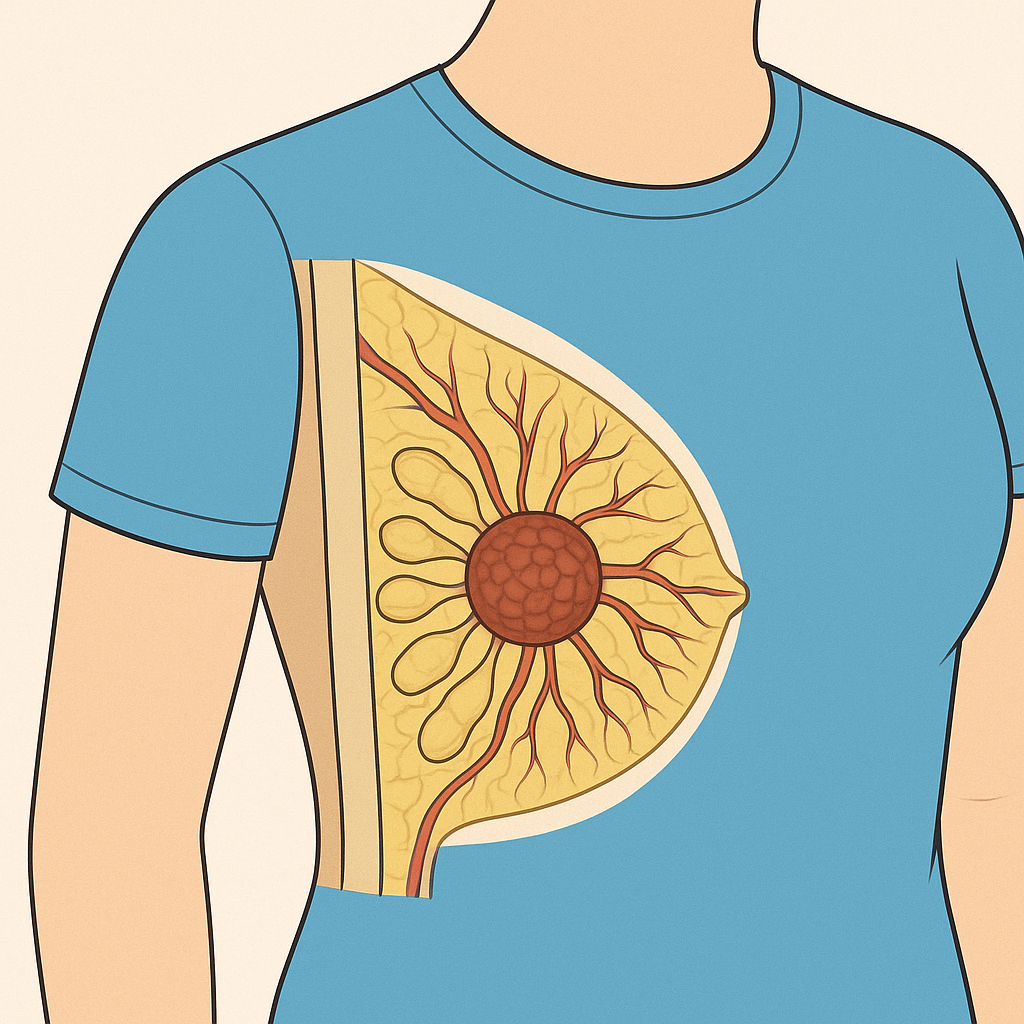

# Female